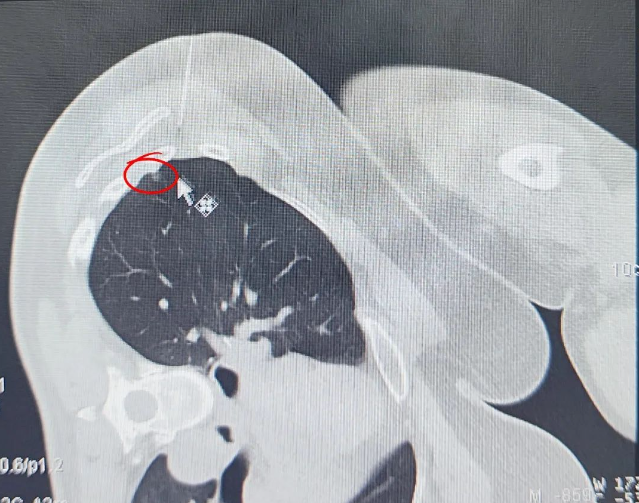

定位技術(shù)升級通過 CT 影像精準(zhǔn)鎖定 6mm 磨玻璃結(jié)節(jié)(圖示可見),全程在麻醉狀態(tài)下完成定位操作,顯著降低傳統(tǒng)清醒定位可能引發(fā)的患者緊張情緒及轉(zhuǎn)運(yùn)風(fēng)險(xiǎn)。微創(chuàng)技術(shù)突破運(yùn)用精細(xì)化微創(chuàng)操作分離粘連組織,在切除病灶過程中精準(zhǔn)避讓正常肺組織,經(jīng)術(shù)后影像評估,實(shí)現(xiàn)病灶完整清除與健康肺功能保留的平衡。